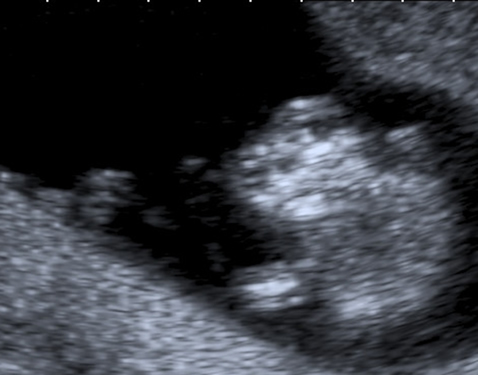

The anencephalic fetus demonstrates no clear frontal bone and often the facial bones may appear unusual also with the orbits appearing prominent – the so called 'frog-eyed appearance'. There may be some brain visible but this is variable. There is no bright skull vault covering the brain.

This image shows the facial view of an anencephalic fetus. Note the frog-eyed appearance. Also note that the skull vault is completely absent.